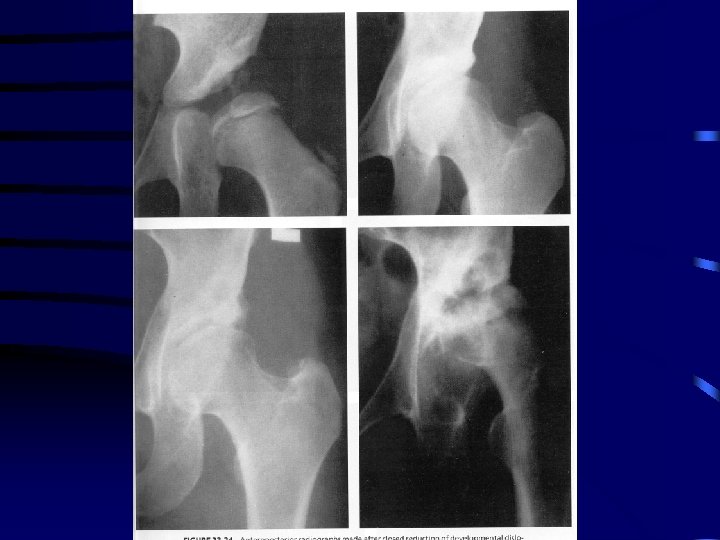

6 months to 2 years age • Closed reduction and spica cast immobilization recommended • traction controversial with theoretical benefit of gradual stretching of soft tissues impeding reduction and neurovascular bundles to decrease AVN • skin traction preferred however vary with surgeon • usually 1 -2 weeks • scientific evidence supporting this is lacking

Treatment con’t • closed reduction preformed in OR under general anesthetic manipulation includes flexion, traction and abduction • percutaneous or open adductor tenotomy necessary in most cases to increase safe zone which lessen incidence of proximal femoral growth disturbance • reduction must be confirmed on arthrogram as large portion of head and acetabulum are cartilaginous • dynamic arthrography helps with assessing obstacles to reduction and adequacy of reduction

Treatment • reduction maintained in spica cast well molded to greater trochanter to prevent redislocation • human position of hyperflexion and limited abduction preferred • avoid forced abduction with internal rotation as increased incidence of proximal femoral growth disturbance • cast in place for 6 weeks then repeat Ct scan to confirm reduction • casting continued for 3 months at which point removed and xray done then placed in abduction orthotic device full time for 2 months then weaned

Complications of Treatment • Worst complication is disturbance of growth in proximal femur including the epiphysis and physeal plate • commonly referred to as AVN however, no pathology to confirm this • may be due to vascular insults to epiphysis or physeal plate or pressure injury • occurrs only in patients that have been treated and may be seen in opposite normal hip

Necrosis of Femoral Head • Extremes of position in abduction ( greater 60 degrees ) and abduction with internal rotation • compression on medial circumflex artery as passes the iliopsoas tendon and compression of the terminal branch between lateral neck and acetabulum • “ frog leg position “ uniformly results in proximal growth disturbance

• extreme position can also cause pressure necrosis onf epiphyseal cartilage and physeal plate • severin method can obtain reduction but very high incidence of necrosis • multiple classification systems with Salter most popular

Salter Classification • 1 failure of appearance of ossific nucleus within 1 year of reduction 2 • 2 failure of growth of an existing nucleus within 1 year • 3 broadening of femoral neck within 1 year • 4 increased xray density then fragmentation of head • 5 residual deformity of head when reossification complete including coxa magna, vara and short neck